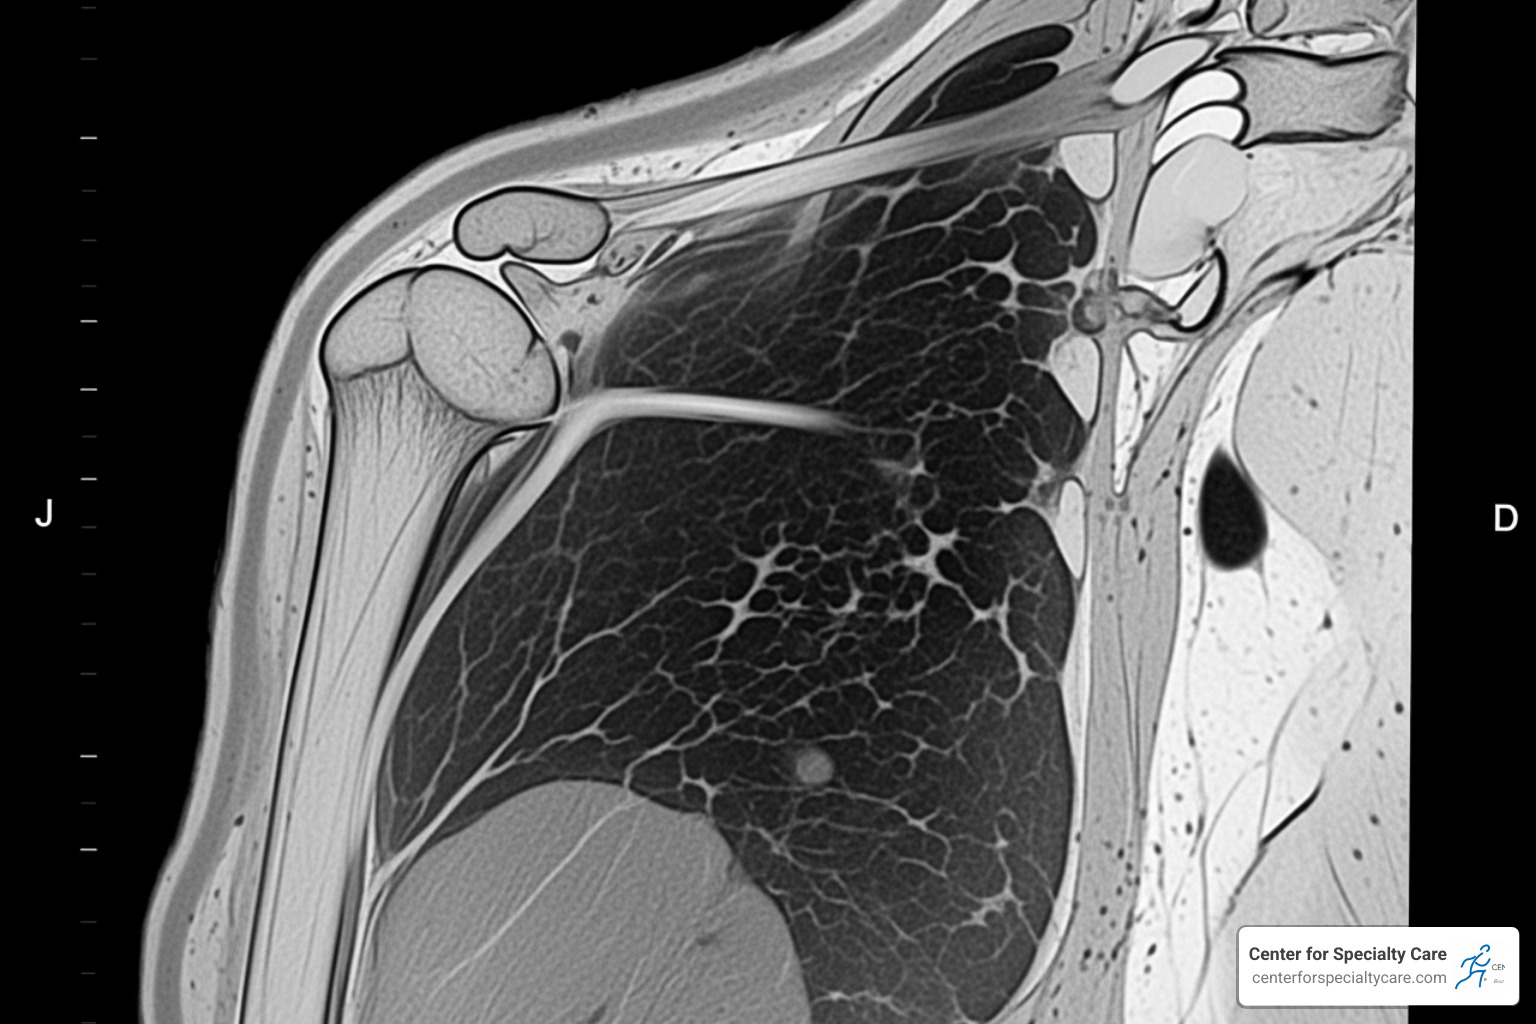

- MRI scans are the gold standard, showing the tear’s location, size (partial or full-thickness), and any muscle changes.

The most common procedure is arthroscopic repair, a minimally invasive technique. We make a few small incisions, insert a tiny camera (arthroscope) to see inside the joint, and use specialized suture anchors to reattach the torn tendon to the bone. For some partial tears, we may perform debridement, which involves smoothing the frayed edges of the tendon. This approach leads to smaller scars and a smoother early recovery.